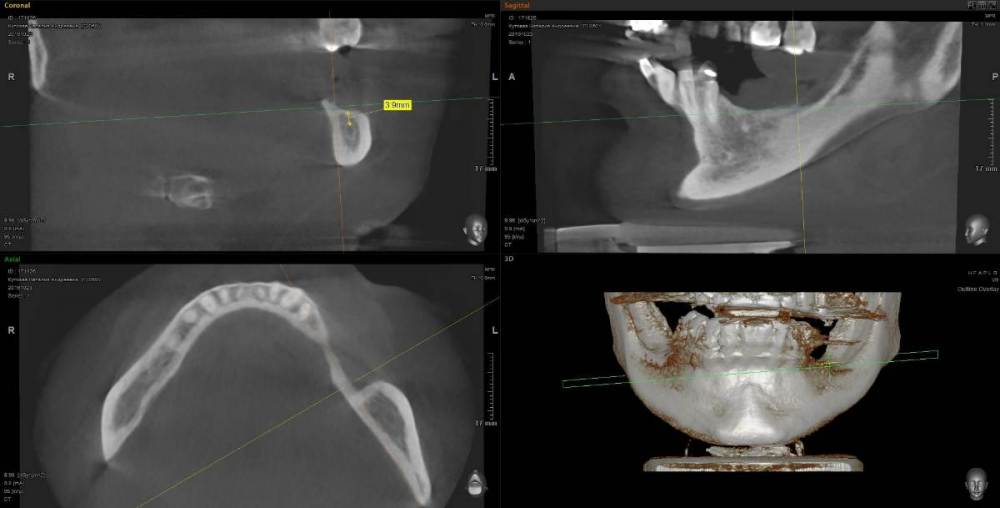

Kostoprav Опубликовано 11 мая, 2021 Поделиться Опубликовано 11 мая, 2021 (изменено) 70%ауто+30% ксено, мембрана цитофлекс, винты самосверлящие после пластики до установки имплантов прошло 8 мес. Изменено 11 мая, 2021 пользователем Kostoprav 3 6 Ссылка на комментарий

Карен Аванесов Опубликовано 12 мая, 2021 Поделиться Опубликовано 12 мая, 2021 20 часов назад, Kostoprav сказал: 70%ауто+30% ксено, мембрана цитофлекс, винты самосверлящие после пластики до установки имплантов прошло 8 мес. Замечательно! 1 Ссылка на комментарий